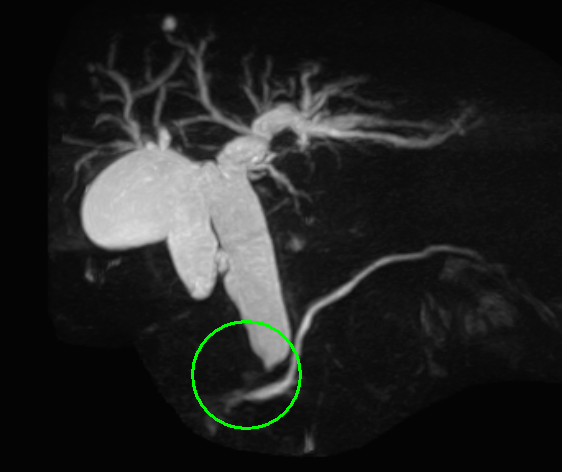

MRI(MRCP)画像